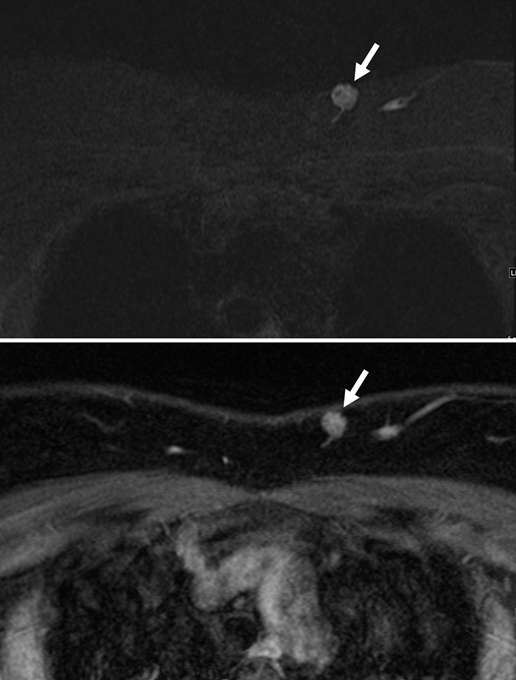

Arteriovenous malformations of the breast are rare. Most cases of breast AVMs are acquired or iatrogenic, either secondary to trauma or following biopsy or surgery. Congenital breast AVMs of are an exceedingly rare clinical entity usually seen in association with other systemic vascular anomalies as part of a syndromic vascular malformation disorder. Initially, a breast AVM may be detected by screening mammography as a nonspecific focal asymmetry or mass, which may trigger subsequent diagnostic breast imaging. The diagnosis can be readily made by duplex ultrasonography as a high-flow complex vascular mass with one or more feeding vessels and a draining vein (Figure 4), with CT or MRI usually reserved for preoperative planning purposes or equivocal cases. Presence of slow or no Doppler flow is more likely to represent a venous/venolymphatic malformation or primary vascular tumor rather than AVM. Treatment is achieved either by endovascular or surgical means. However, there is a paucity of literature on the appropriate management, and no guideline currently exists as the gold standard of care. Therefore, patients with breast AVMs should be evaluated by a multidisciplinary team at a center with a dedicated vascular malformations practice.